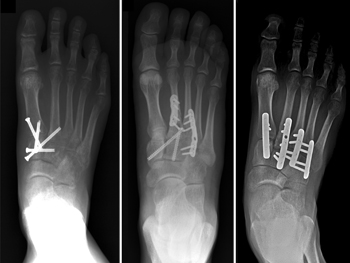

Internal fixation. In this procedure, the bones are positioned correctly (reduced) and held in place with plates or screws. Because the plates or screws will be placed across joints that normally have some motion, some or all of this hardware may be removed at a later date. This can vary from 3 to 5 months after surgery, and is at the surgeon's discretion.

Various methods of internal fixation can be used to fix Lisfranc injuries. (Left) Multiple screws can be used. (Center) A combination of plates and screws are sometimes required when fractures are present in addition to a torn ligament. (Right) Plates that span the joints are also an excellent method of fixation.